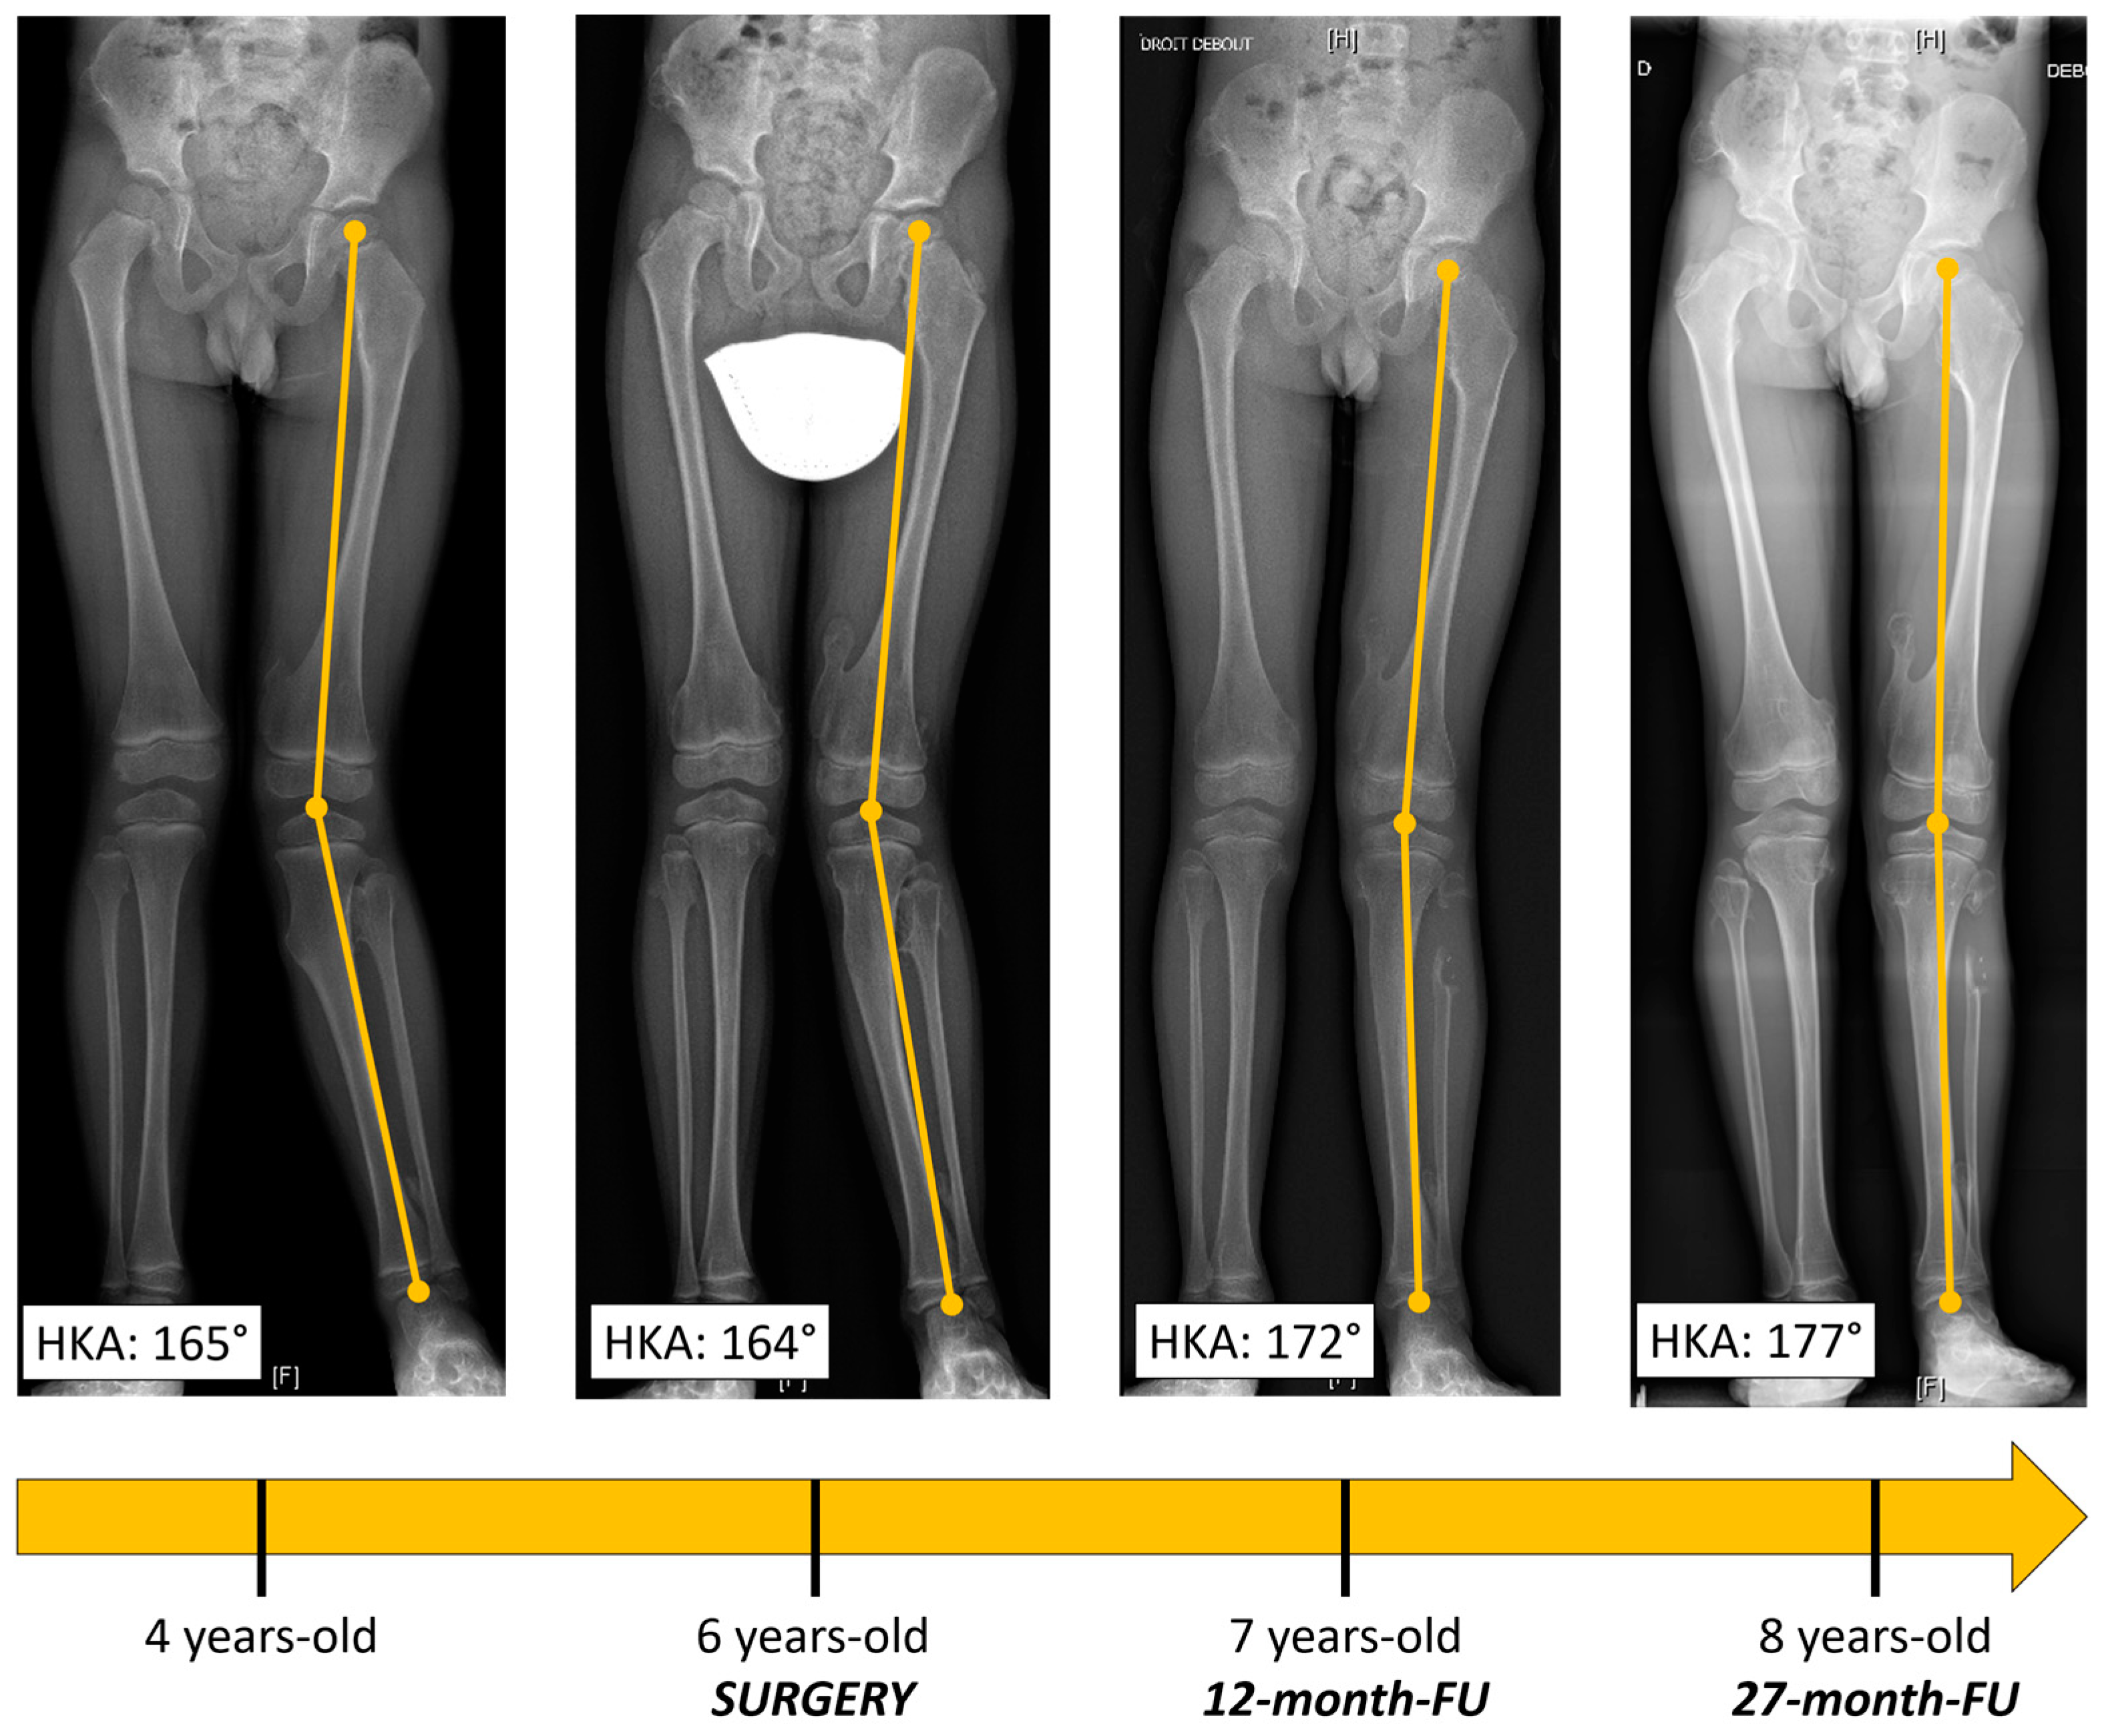

Radiography (Figure 1a,b) revealed a voluminous inter-tibio-fibular osteochondroma developed from fibular proximal metaphysis. The approximate dimensions of the bone tumor were about 4/3/2 cm (cranio-caudal/antero-posterior/latero-lateral). The lesion had all the characteristics of an exostosis [3]: benign-appearing bone lesion, bony excrescence with well-defined margins, thin outer cortex which flares from the host bone cortex and internal lesion in cancellous bone which blends with the cancellous bone of the metaphysis [3]. There was no sign of adjacent bone scalloping, but bowing of the tibia was present. We also performed an MRI exam which confirmed the lesion and showed close relation to the tibiofibular trunk and the anterior tibial artery, but without any sign of compression (Figure 1c). Long-leg radiographs showed valgus deformity of the tibia (HKA angle: 166°, MAD: 29 mm) (Figure 2).

As for follow-up, the patient was evaluated every six weeks during the first three months and every six months until the first two years after surgery. The patient presented a gradual improvement of the valgus deformity. At 27 months postoperative, he was asymptomatic with a full range of motion of the knee, no clinical deformity and no knee frontal laxity. Long-leg radiographs showed the complete correction of the tibia valga (HKA: 178° AND MAD < 5 mm) (Figure 2, Table 1). Notably, due to extraperiosteal resection, there was no sign of bone union at the proximal fibula. Tibial bowing improved as well (Figure 4). Lateral release of the fibula led to an increase in the fibula/tibia index (from 93% preop to 96% at follow-up), resulting in valgus deformity improvement (Figure 5, Table 1). Using a Pearson correlation test, we found that HKA and fibula/tibia index were strongly correlated (R = 0.9390, p < 0.001).

Figure 2. Long-leg X-rays showing gradual improvement of valgus deformity throughout follow-up.